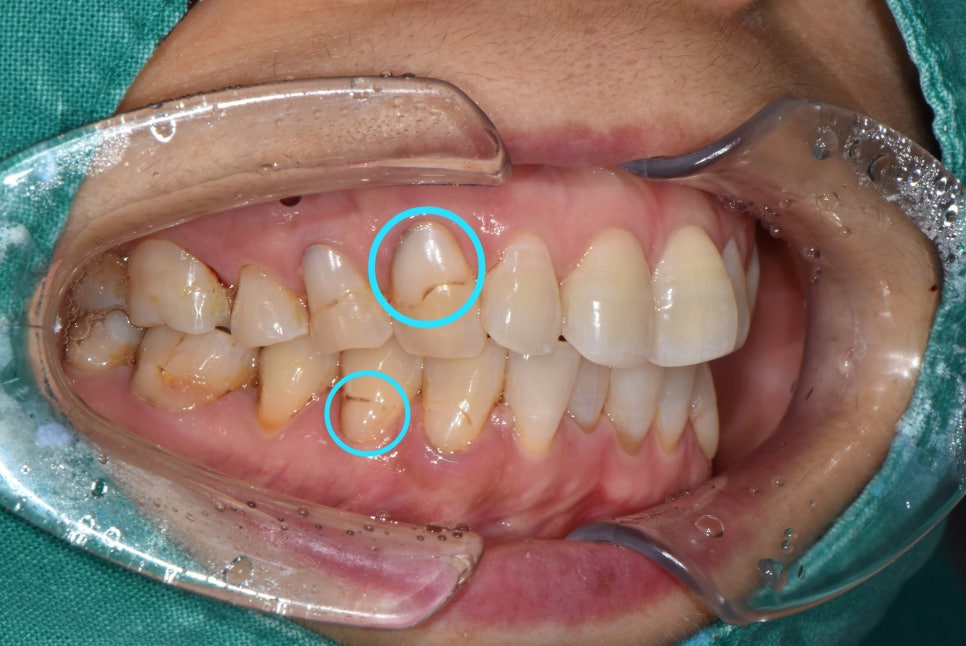

안녕하세요. 의정부 <바른손 치과>입니다. 오늘은 착색 제거에 대해서 설명드리고 보여드리려합니다. 착색 제거는 미백치료를 해야만 한다고 생각하실 수 있는데요. 치아 전체를 미백하지 않고 부분적으로 착색된 치아들만 깨끗하게 하실 수도 있습니다. 미백을 하지 않았지만 착색 제거만으로 치아를 깨끗하게 해드렸던 케이스를 보여드릴게요! 전체적인 검진과 스케일링을 하러 오셨던 환자분입니다. 치아를 확인해보니 치경부 마모증으로 인해 레진치료를 하셨고 레진 충전물과 치아의 경계부에 착색이 되어있으셨습니다. 이런 충전물을 다 떼어낸 후 다시 하기에는 너무 아깝잖아요? 시간도 들고.. 비용도 들고.. 그렇기 때문에 기존 충전물을 더 오래 사용하실 수 있도록 레진 착색제거를 시행하였습니다! 충전물 연마로 착색 제거를 한 후 사진입니다. 더 비교하기 쉽게 사진을 보여드릴게요! 동일 부위 비교 사진을 보시면 확실히 연마 전 사진보다 환하고 깨끗해진 치아가 된게 보이시나요?? 간단하게 다듬기만 했을 뿐인데 더 건강한 치아처럼 보이네요 ㅎㅎ 충전물을 새로 안 해도 되고 너무 깔끔해졌다고 환자분도 만족 하셨답니다! 이렇게 깨끗하게 만든 치아를 다시 착색되도록 할 순 없겠죠!? 치아가 착색되지 않게 하려면, 흡연이나 커피, 홍차, 와인, 카레와 같은 음식들을 되도록 피해주시고 식사 후 바로 양치질 하시는 습관이 제일 좋습니다. 오늘은 이렇게 치아 착색 제거 케이스를 보셨는데요. 다음번에 더 유익하고 좋은 정보를 가지고 오겠습니다ㅎ 환자분의 심미적인 치아를 생각하는 의정부 <바른손 치과>였습니다. 감사합니다! |